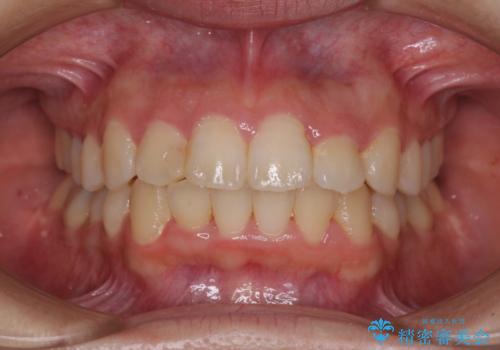

1日22時間の装着時間をしっかり守ってくださったので、予定していた1年よりも早く治療を終えることができました。

インビザライン矯正特有の奥歯がしっかりと咬合しない感覚も改善され、大変満足していただきました。